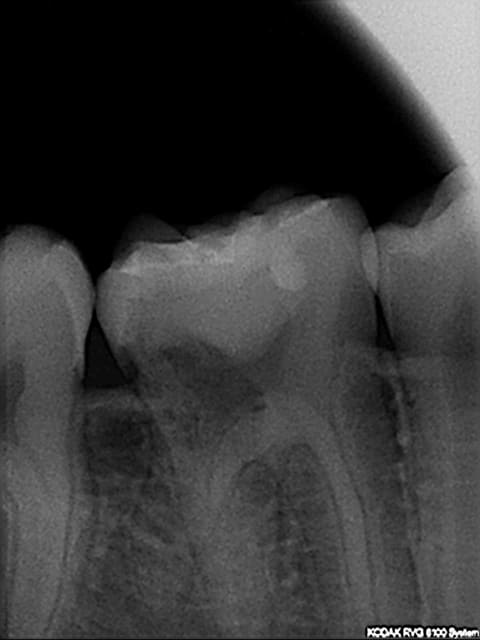

Le traitement est donc le suivant :

application d'une solution à 90% d'acide trichloracétique sur le tissu de résorption

curetage

restauration avec un verre ioniomère.

traitement endo si nécessaire.

Parfois extrusion ortho dans certains cas.

Quoiqu'il en soit, c'est pas gagné car dans ton cas, elle est en stade 3...

L'application d'acide et la mise en place du cvi doit se faire par l'extérieur si j'ai bien compris.(en essayant de ne pas renter dans la chambre). c'est chaud car c'est volumineux !

J'ai pas tout compris à ta dernière phrase, mais j'imagine que tu fais allusion à la présence de racines individualisées au niveau de cette 46.